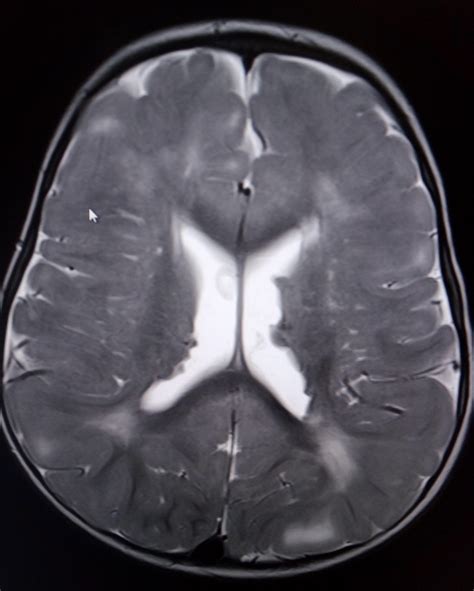

The central nervous system is frequently involved in TSC, leading to significant neurological morbidity, including epilepsy, cognitive impairment, and autism spectrum disorder. Imaging studies, particularly Magnetic Resonance Imaging (MRI), are the gold standard for evaluating these intracranial manifestations.

The hallmark brain lesions in Tuberous Sclerosis Radiology include:

• Cortical Tubers: These are areas of cortical dysplasia, appearing as hyperintense signals on T2-weighted and FLAIR MRI images. They are most commonly found in the frontal lobes.

• Subependymal Nodules (SENs): Small, benign nodules located along the walls of the lateral ventricles. They are often calcified and can be easily visualized on both CT and MRI scans.

• Subependymal Giant Cell Astrocytomas (SEGAs): These are tumors that typically arise from SENs near the foramen of Monro. Unlike static nodules, SEGAs have the potential for growth and can cause obstructive hydrocephalus, requiring urgent surgical or pharmacological intervention.

• White Matter Radial Migration Lines: These appear as linear bands of hyperintensity extending from the periventricular region toward the cortex, representing disrupted neuronal migration.